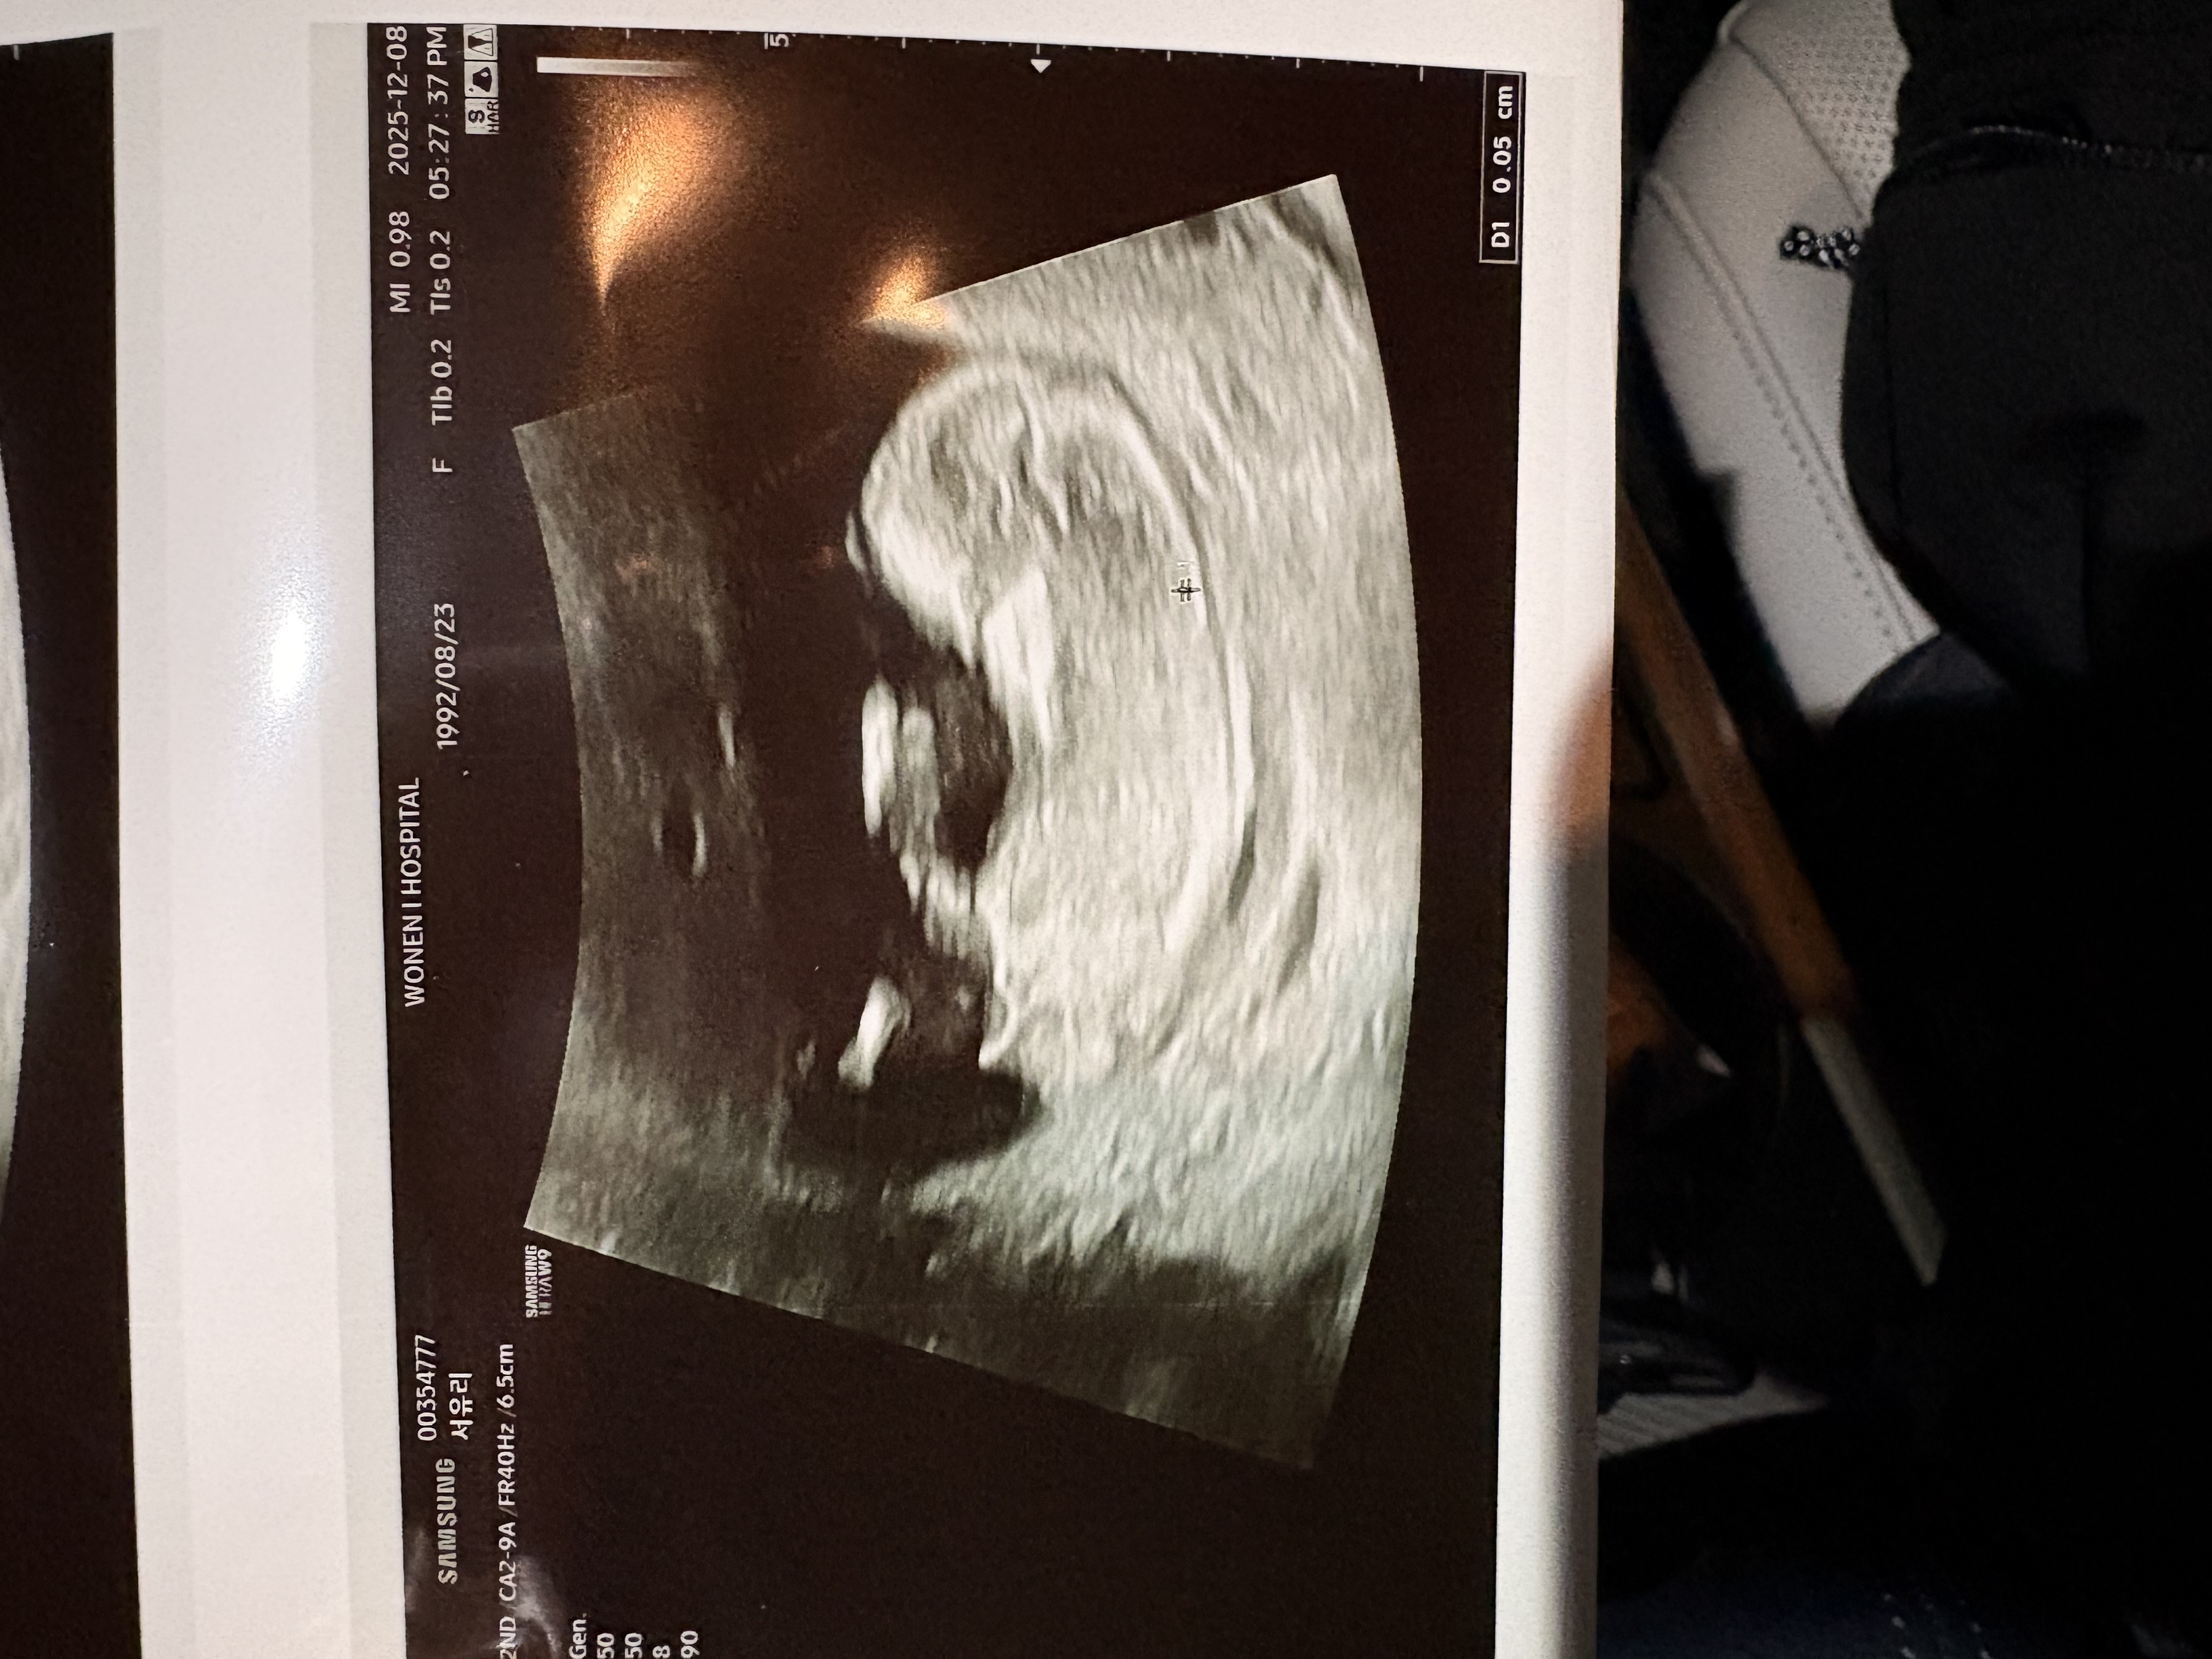

성별 투표해주세용

11주차입니당